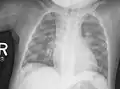

La radiologie confirme le diagnostic, et il est inutile de les multiplier. Le défaut de minéralisation des os longs s'observe particulièrement sur les radiographies de face d'un poignet et des genoux : retard ou irrégularités des points d'ossifications attendus pour l'âge (maturation squelettique), lignes métaphysaires irrégulières donnant un aspect « en toit de pagode », la corticale de la diaphyse est amincie, la densité osseuse est diminuée donnant un aspect vermoulu. Les os longs s'incurvent.

Au niveau du thorax, le chapelet costal clinique donne un aspect radiologique, surtout visible de profil, « en bouchon de champagne » des jonctions chondro-osseuses. En sus des déformations osseuses, on peut observer des atteintes pulmonaires par troubles de la ventilation.

Radiographie du thorax.